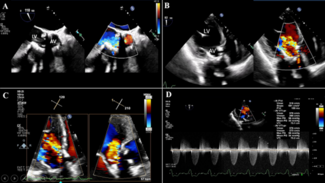

Clinical Images

12/29/2025

Konstantinos Stathogiannis, MD, FACC; Michael Chrissoheris, MD; Kyriakos Katsianos, MD; Vivi Grammata, MD; Alexis Dimas, MD; Konstantinos Spargias, MD

An 81-year-old woman with prior surgical aortic valve replacement presented with progressive dyspnea . Echocardiography showed severe bioprosthetic aortic stenosis with mild paravalvular leak and preserved ejection fraction.